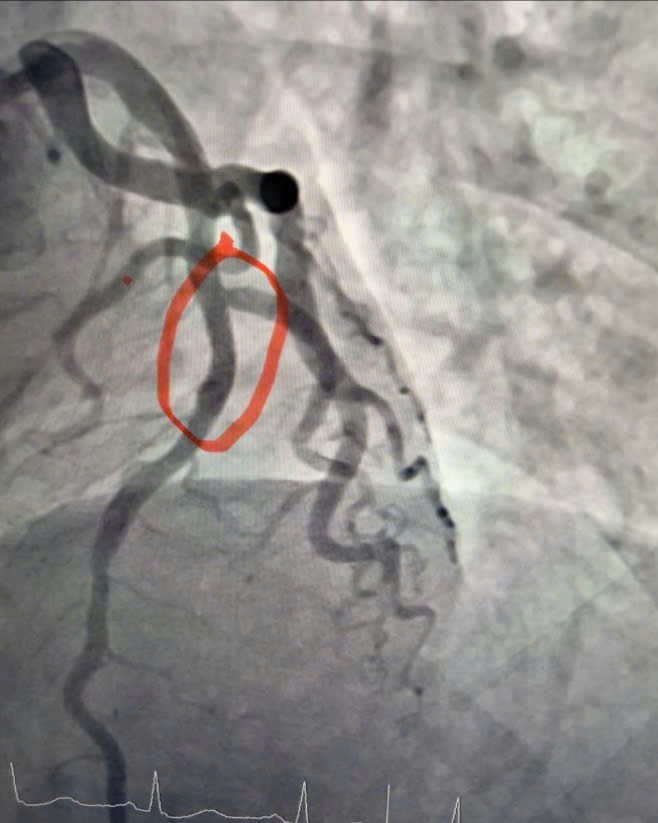

Hình ảnh chụp động mạch vành cho thấy hẹp 95% đoạn 1 động mạch liên thất trước – nhánh thủ phạm gây nhồi máu cơ tim cấp.

Ê-kíp bác sĩ Khoa Nội Tim mạch đã tiến hành chụp động mạch vành, kết quả cho thấy động mạch liên thất trước đoạn 1 – nhánh thủ phạm gây nhồi máu – bị hẹp tới 95%. Người bệnh được can thiệp nong và đặt stent động mạch vành, giúp tái thông dòng máu nuôi cơ tim, hạn chế tối đa tổn thương cơ tim và các biến chứng nguy hiểm.